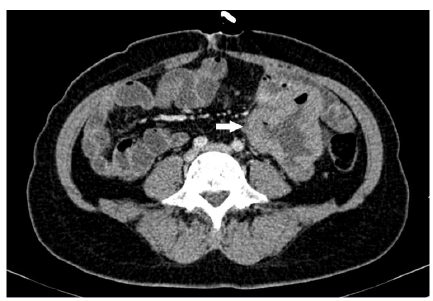

A Case of Small Bowel Lymphoma in a Patient with a History of Parotid Melanoma

Ennmer Mohammed, Elbakkari Asaad, Zerhari Yassine, Essaber Hatim, Omor Youssef and Latib Rachida. 10(5): 01-02.